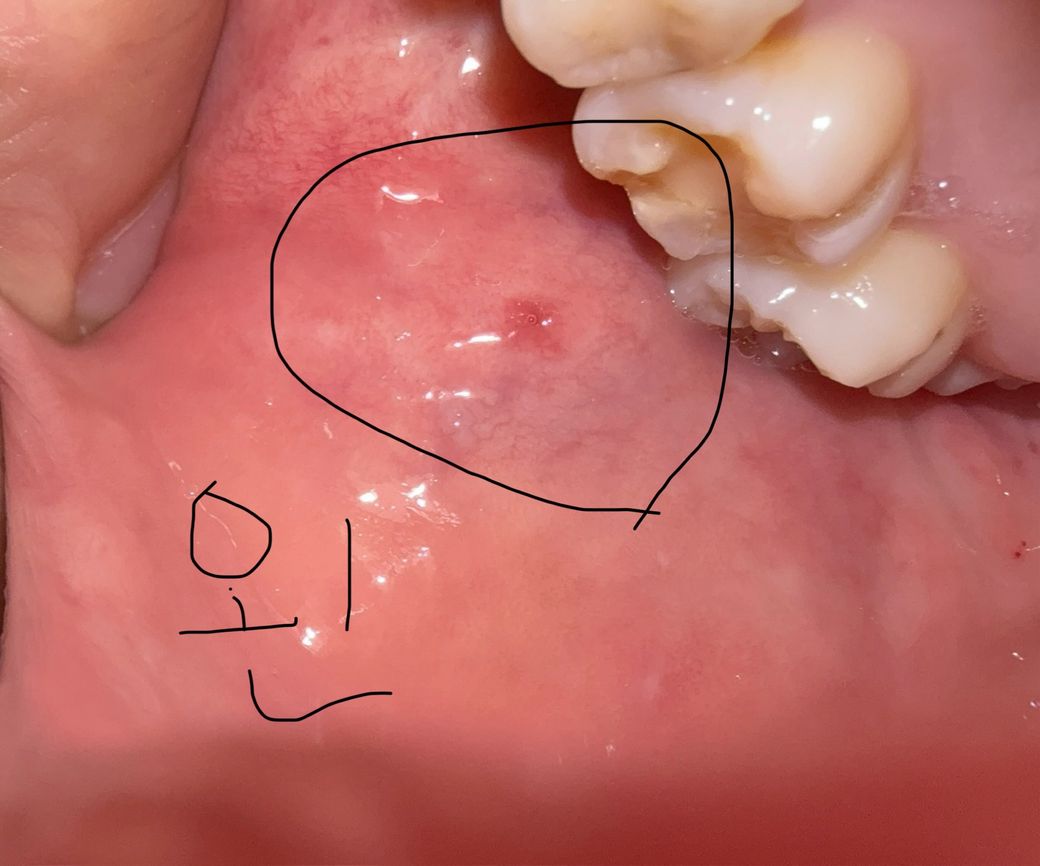

구강암 의심해도 되는지 봐주세요ㅠㅠ

한달 반 정도 부터 볼쪽에 혀로 만졌을때 염증같은 느낌이 나는데 특별한 통증은 없는데 이게 생긴뒤로 혓바늘이 자주나고 가끔 오른쪽 아래턱뼈가 저리는 느낌을 받고 침 삼킬때 목에 가시걸림 느낌도 있는거 같고 여러모로 불안한 마음에 올려봅니다ㅠㅠ 또 병원을 가서 검사를 한다면 무슨병원을 가야할지 알려주시면 감사하겠습니다.

• 1번 째 사진

병소 양상이 경계가 명확하고 출혈성도 아니고, 경결감도 보이진 않으므로 악성 가능성은 낮습니다 구강내과가서 추가적인 진단 받아보세요